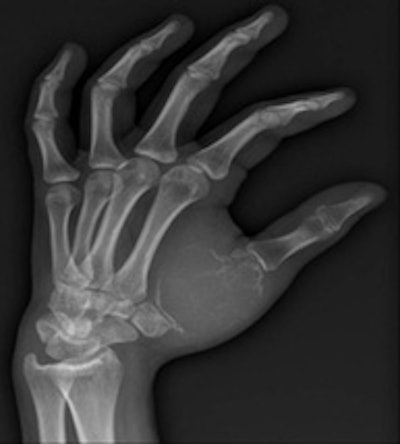

Bilbao's keen interest in interventional radiology began during the third year of his residency in 1982.

In the third year of my residency in 1982, I began to be attracted by the new way to perform interventions through percutaneous and endovascular approaches, and for a few months I went to the MD Anderson Center in Houston, Texas, U.S. There I took an important decision, which was that I would like to be completely involved in interventional radiology (IR), and with the great support of the CUN, this is what I have done for the rest of my professional life.